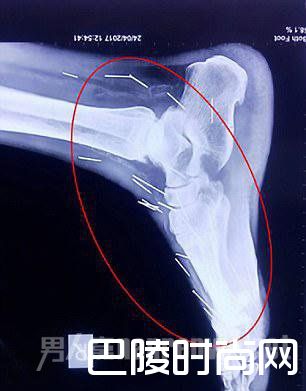

脚踝中的银针

米纳的儿子表示,他的父亲因感到疼痛所以到医院进行脚部手术,检查后才发现原来疼痛来自于这些针。他说:“我看到X光照片后感到非常害怕,我问过父亲数次,他都表示没有相关记忆。”